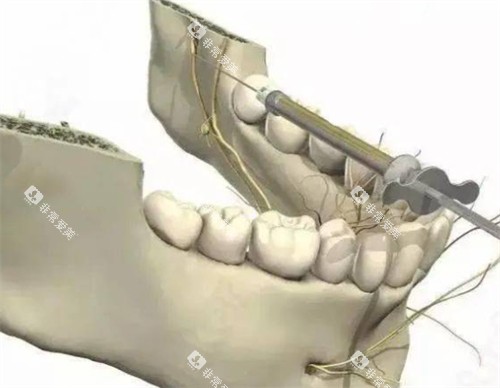

对于一些复杂的口腔手术,如种植牙、正畸治疗等,长治第二人民医院口腔科也有着较高的性价比。

在种植牙方面,科室引进了多种比较有名品牌的种植体,价格涵盖了不同的档次,患者可以根据自己的经济实力进行选择。

同时,医生娴熟的种植技术能够确保种植结果,大大提高了种植牙的成功几率。